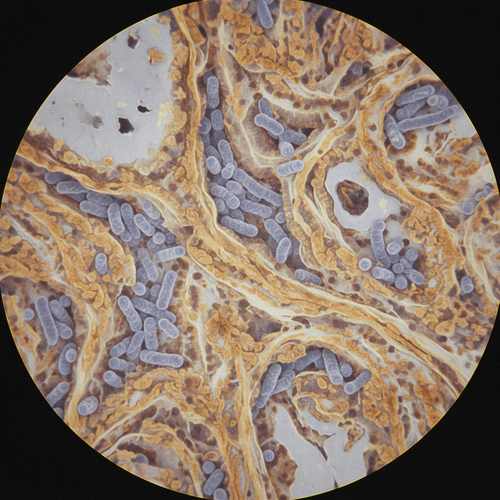

The challenge lies in differentiating between ILD exacerbation and TB infection. Both can present with similar symptoms: cough, dyspnea, and fatigue. High-resolution CT (HRCT) findings can also overlap, with both conditions potentially showing ground-glass opacities, consolidation, and even cavitation. The insidious nature of TB, particularly in immunosuppressed individuals, further complicates the picture. In this particular case, the initial clinical picture was attributed to ILD progression, leading to a delay in TB diagnosis. The key here is to recognize that in TB-endemic areas, any worsening respiratory symptoms in an immunosuppressed SSc patient should trigger a thorough TB workup, including sputum cultures, PCR testing, and possibly bronchoscopy with bronchoalveolar lavage.